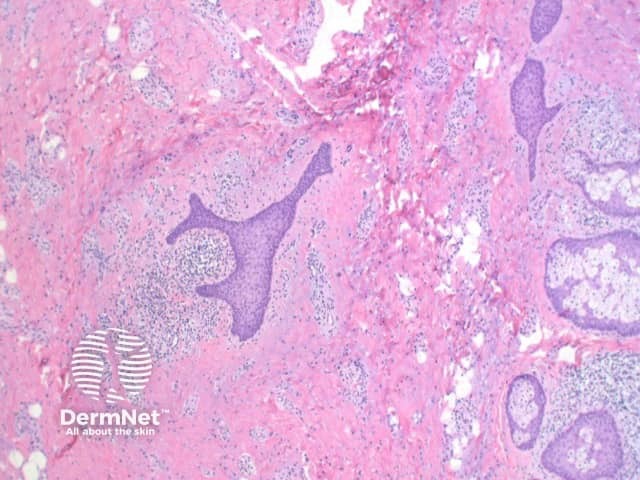

Scanning view shows dilated follicular structure or structures, with radiating mature sebaceous lobules (figures 1, 2). Surrounding the distorted hair follicles there may be thin anastomosing epithelial strands (figure 3). The stroma surrounding the epithelial units is frequently composed of dense collagenous tissue (figure 1-3) and can show prominent clefting to the surrounding adjacent uninvolved dermis (figure 1). Additional stromal changes can include increased vascularity or pockets of adipocytes consistent with increased stromal fat (figure 4).

Figure 3